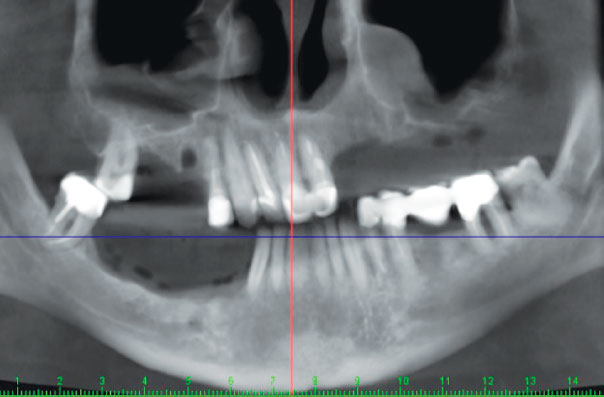

До начала стоматологического лечения выполнена компьютерная томография (КТ) зубов верхней и нижней челюсти (рис. 3).

Рис. 3. Компьютерная томограмма зубов верхней и нижней челюстей до начала стоматологического лечения

Fig. 3. Computed tomography scan of the maxillary and mandibular teeth before dental treatment